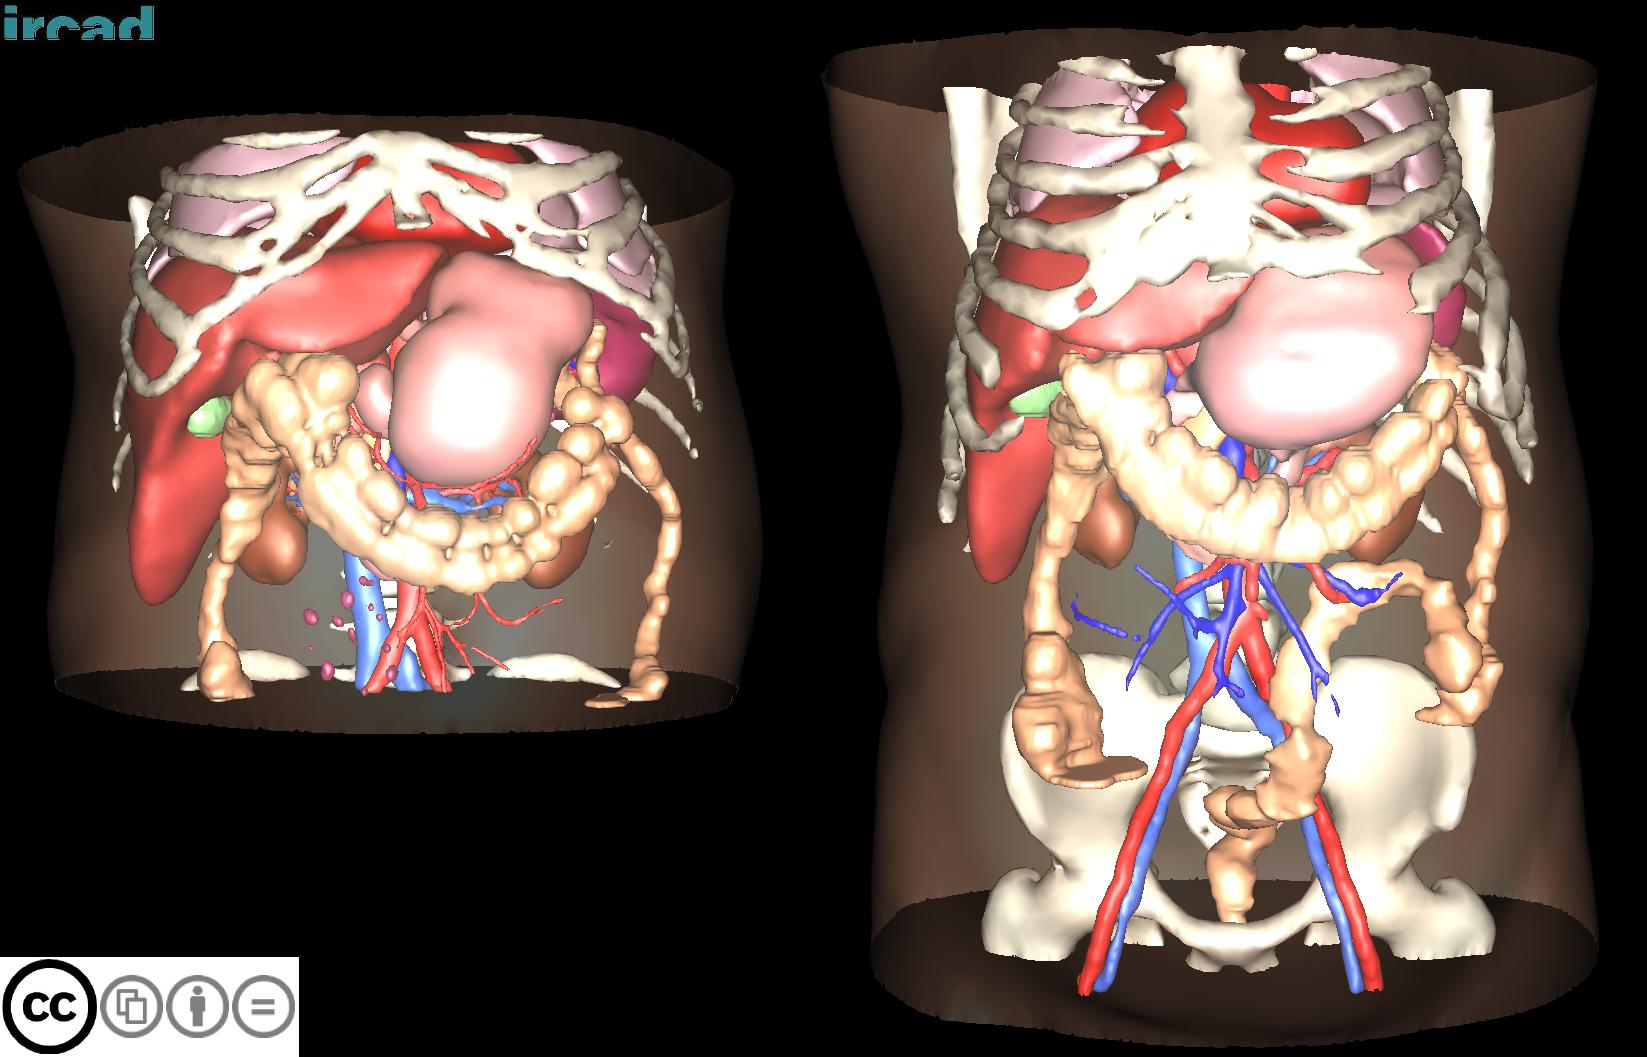

## 3D-IRCADB

| 3D-IRCADb [01](https://www.ircad.fr/research/3d-ircadb-01/) [02](https://www.ircad.fr/research/3d-ircadb-01/) | 肝脏/肝肿瘤 | 分割 | CT | 20+2 | surface mesh | dcm |

3D-IRCADb是比较早的一个数据集,有两个子集,分别包含20组和2组CT片子。

[Aistudio下载](https://aistudio.baidu.com/aistudio/datasetdetail/10293)